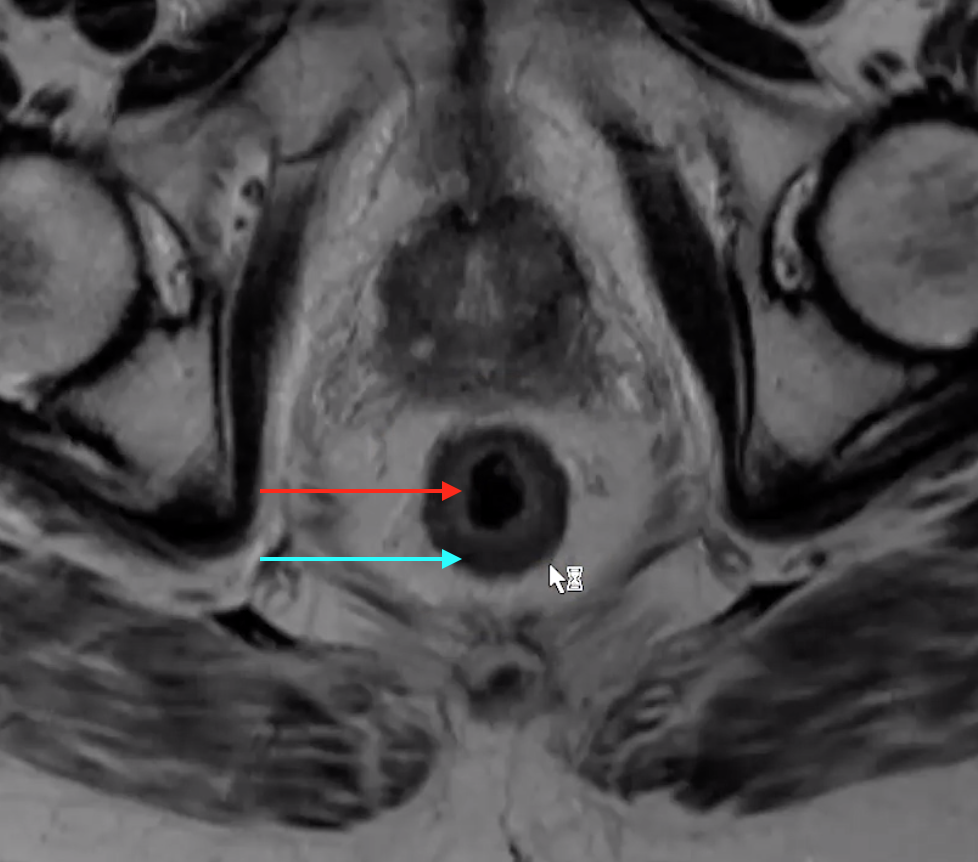

Anal Sphincters

• External sphincter

• Darker external line (blue)

• Extends slightly lower than internal

• Internal sphincter

• The brighter/white internal stuff (red)

Rectal Wall

• Muscularis

• Darker external ring (blue)

• Mucosa

• Made up of the mucosa and submucosa but these cannot be differentiated on imaged they run together